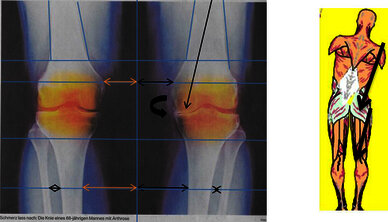

Oberkörper seitliche Ausweichhaltung führt über die Hebelwirkung zu Überbelastung der Knie-Innenseite (Folge Arthrose wird festgestellt?)

Dieses Beispiel:

Abgenutzter Knorpel

Ursache: Seitliche Oberkörper

Ausweichhaltung

Becken Bild 1

Anhand der Original Aufnahmen werden Spannungsbedingte Ausweichhaltungen auf den folgenden Seiten sichtbar gemacht.